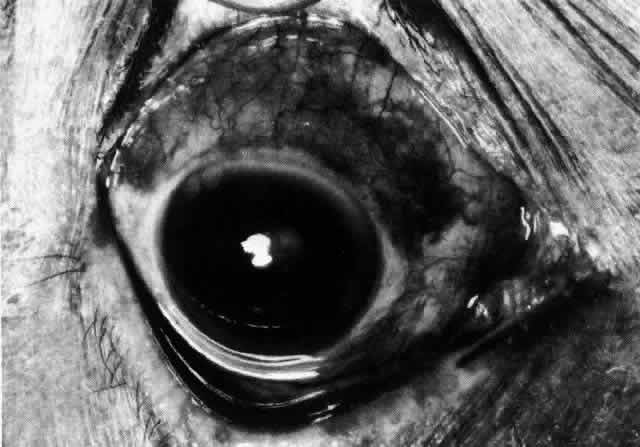

In contrast to simple episcleritis, the infiltration and edema of nodular episcleritis are localized to one part of the globe, forming a nodule and some surrounding congestion (Color Plate 1B). The nodule can be moved over the underlying sclera, which is not edematous. The scleral plexus of vessels can be distinguished deep to the nodule, lying flat on the sclera and slightly congested but otherwise normal in color and configuration (Figs. 15 and 16). Episcleral nodules may be single or multiple but do not undergo necrosis (see Fig. 16). After multiple attacks of nodular episcleritis in the same location, the superficial lamellae of the sclera show some alteration and become slightly more transparent in this one area.

Fig. 15. Episcleritis. In episcleritis, the vascular networks of the conjunctiva, episclera, and sclera are all congested. The edema is confined to the episcleral tissue so that the reflected light from the sclera shows no displacement. (Watson PG, Hayreh S, Awdry P: Episcleritis and scleritis. Br J Ophthalmol 52(3):278–279, 1968)

Fig. 16. Deep vessels, which are normal in configuration, can be traced beneath edematous nodules lying flat on the sclera. (Watson PG: Connective tissue disorders and the eye. In: Recent Advances in Ophthalmology, Vol 5, pp 214–277. London, Churchill-Livingstone, 1975)